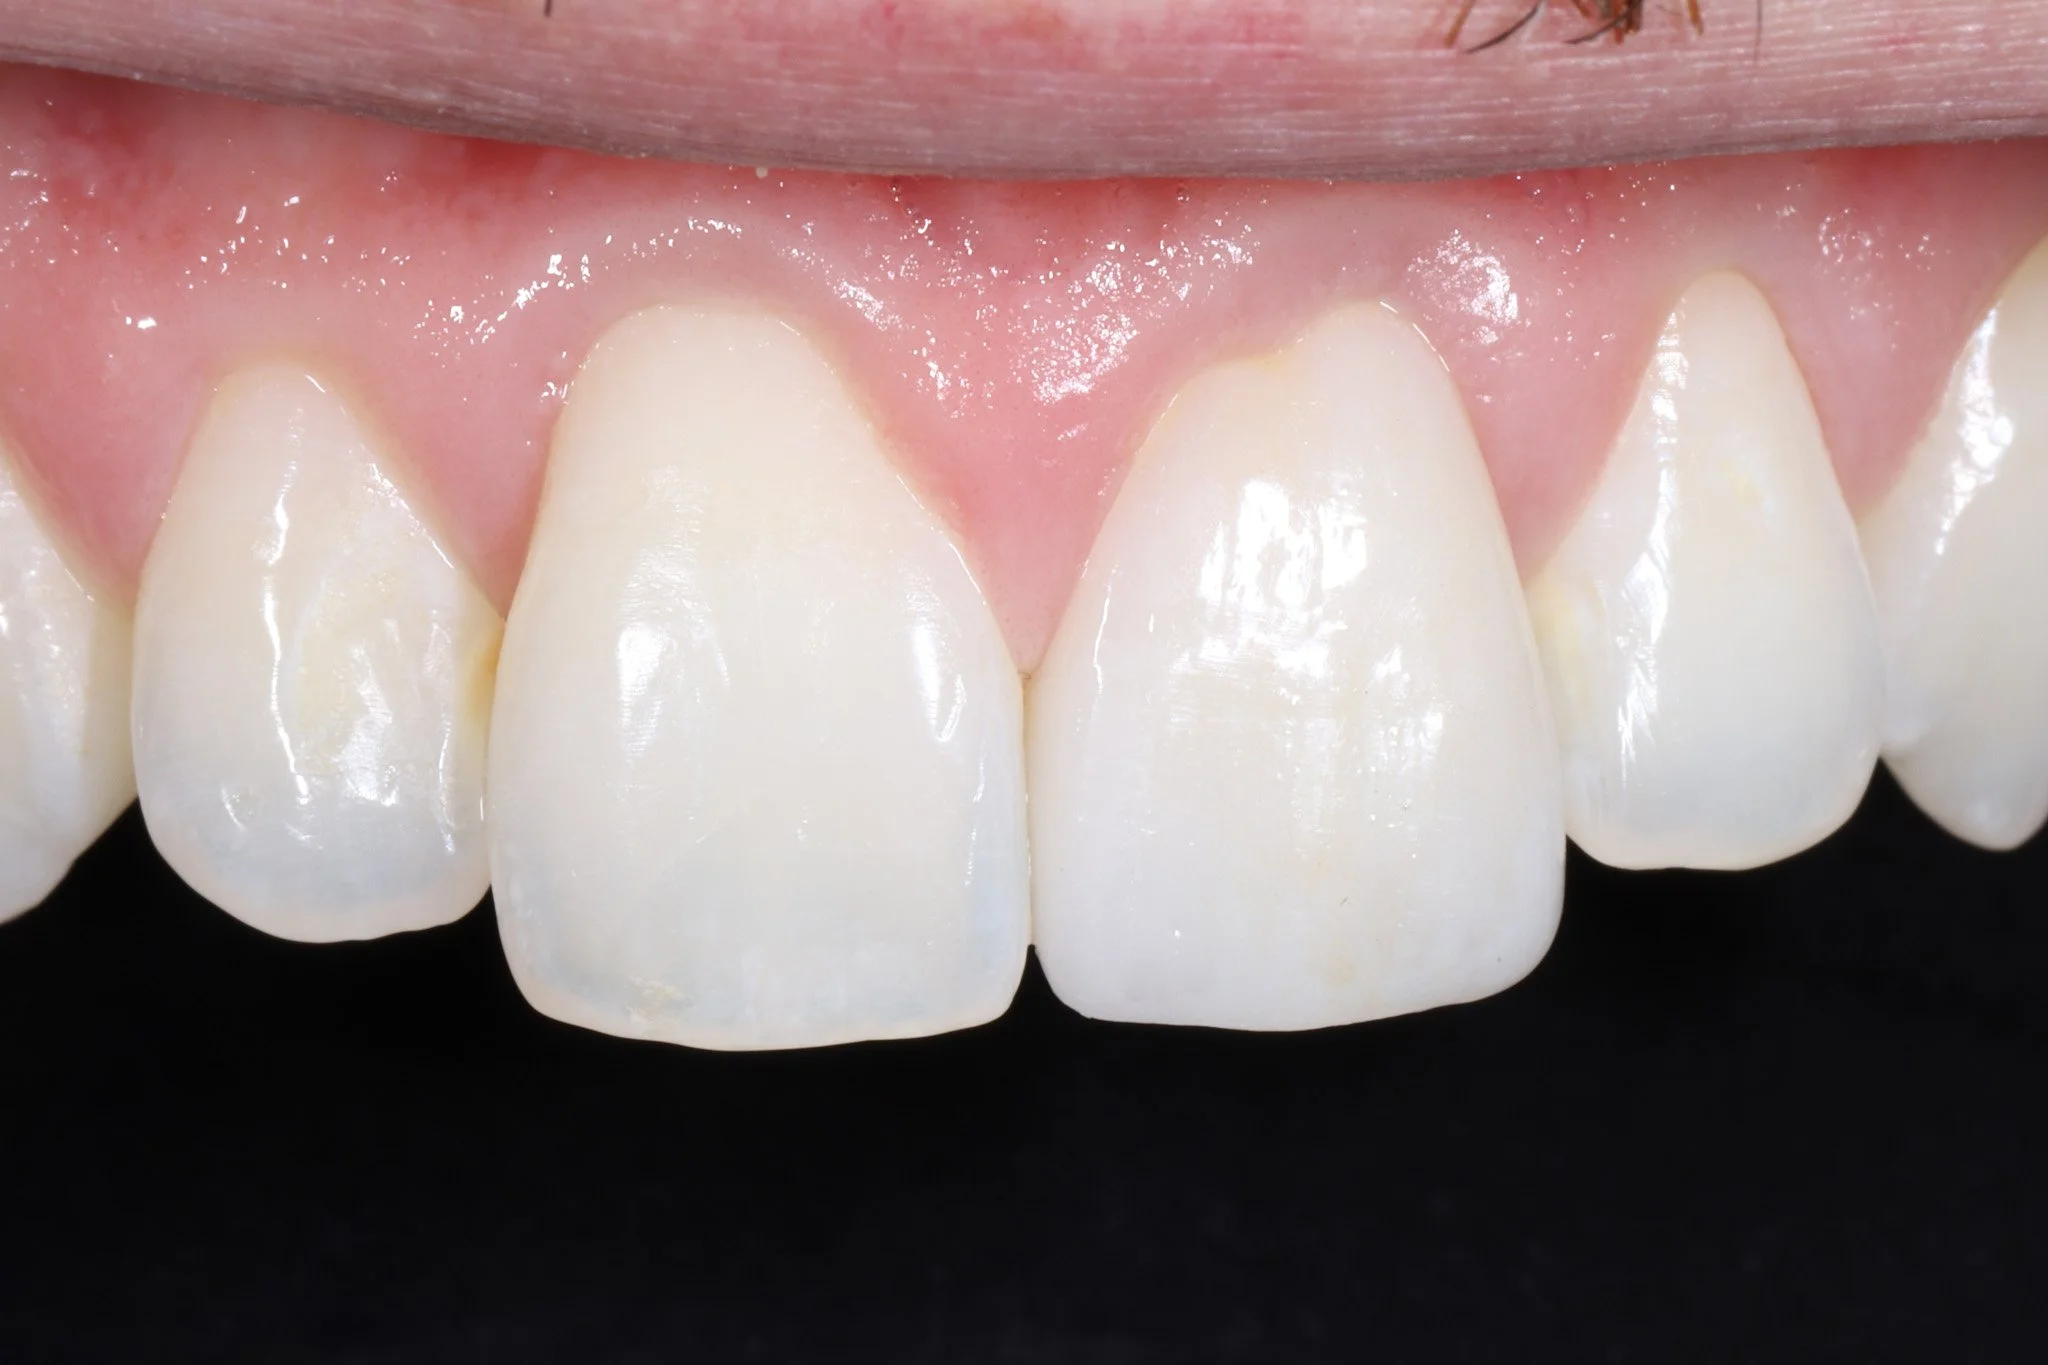

Close-up image of upper front teeth showing mismatched crowns, chipped and worn teeth with acid erosion.

Before: Heavy acid erosion, wear, poor aesthetics

Close-up of a person's upper front teeth, showing straight, white teeth with healthy gums with ideal aesthetics.  These teeth were restored with porcelain crowns.

After: Protected teeth with proper aesthetics and function